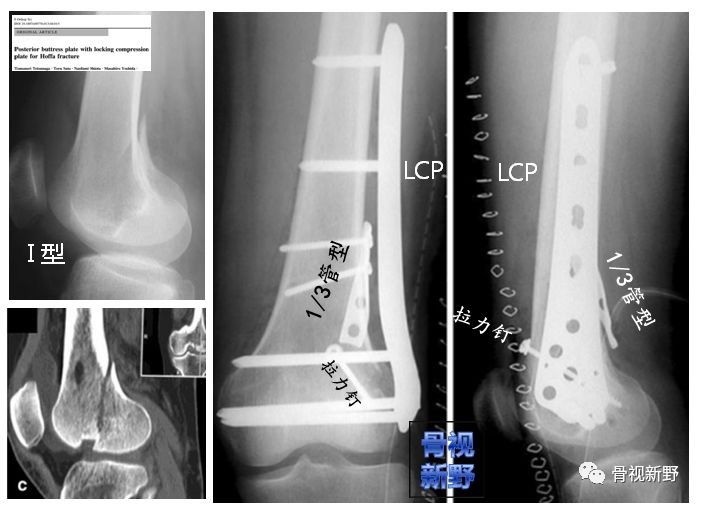

小直径拉力螺钉+1/3管型钢板(扭转)后外侧Buttress+外侧LCP中和钢板

小直径拉力螺钉+LCP侧方支持钢板+后方Buttress钢板